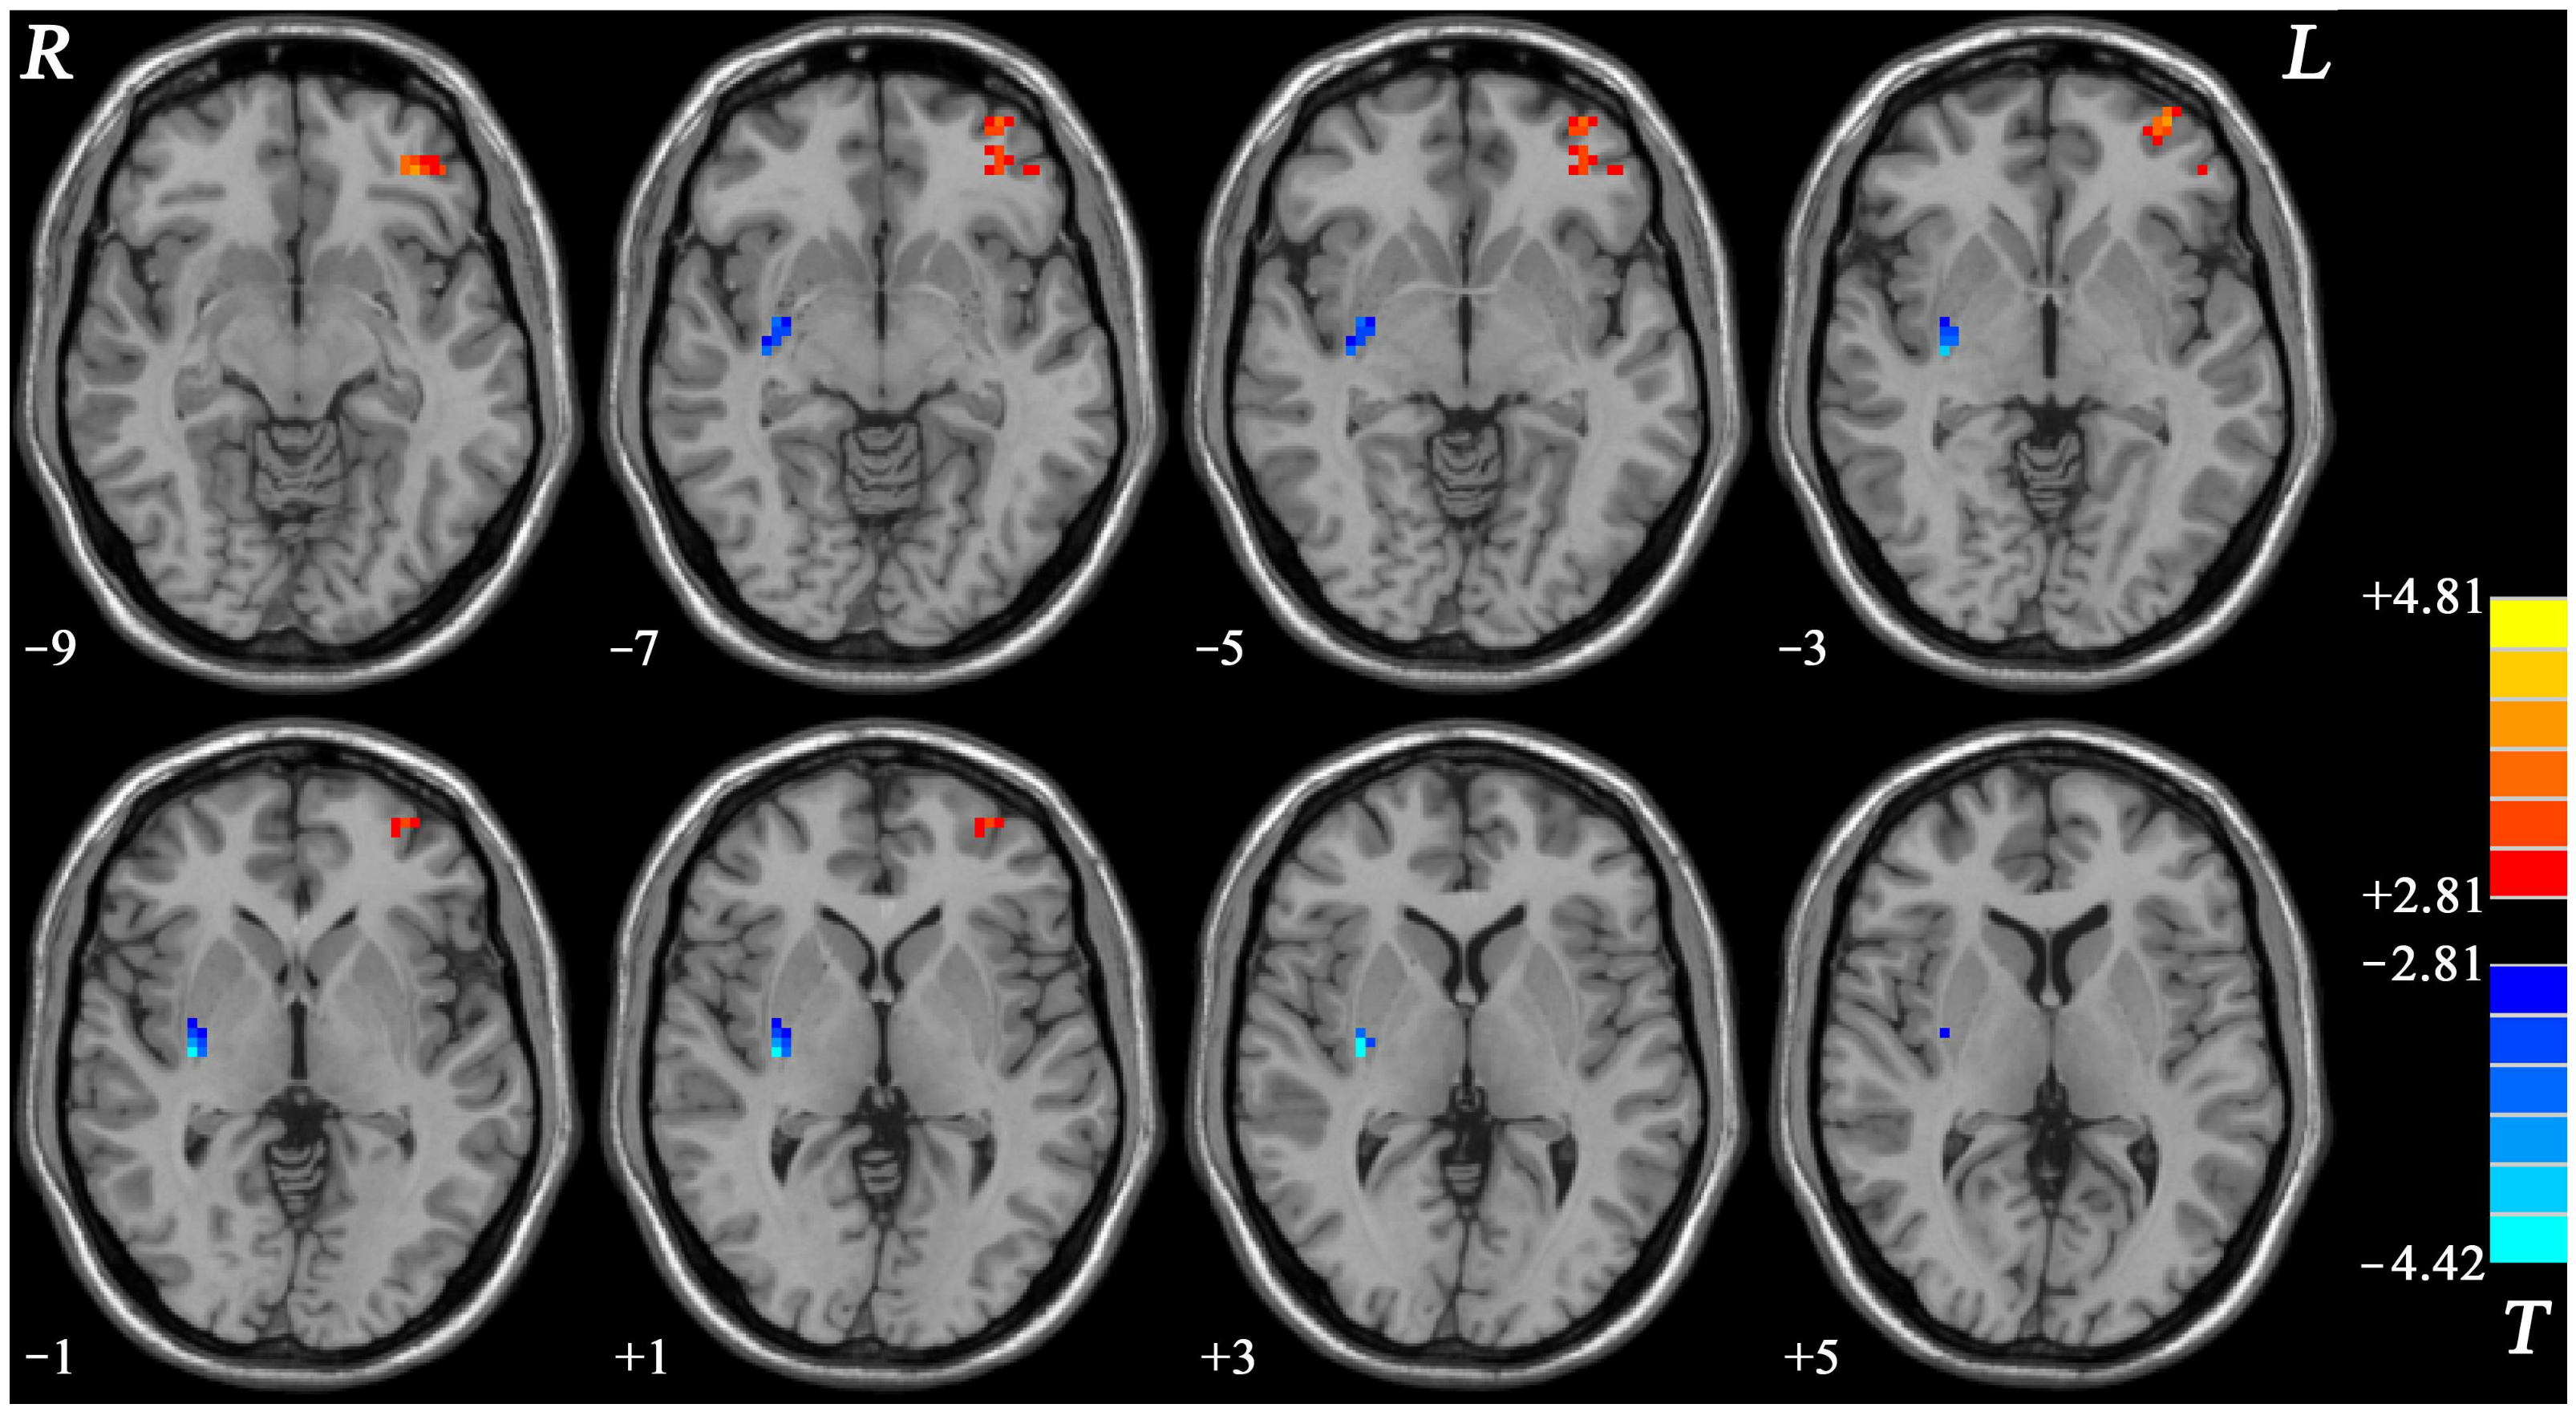

3.3. Group Deviations of NH within the Fronto-Limbic Network

| Cluster Location | Peak (MNI) | Number of Voxels | T Value | ||

|---|---|---|---|---|---|

| x | y | z | |||

| NH | |||||

| left OFC | −36 | 42 | −9 | 50 | 4.0674 |

| Right putamen | 33 | −12 | 3 | 25 | −4.4232 |